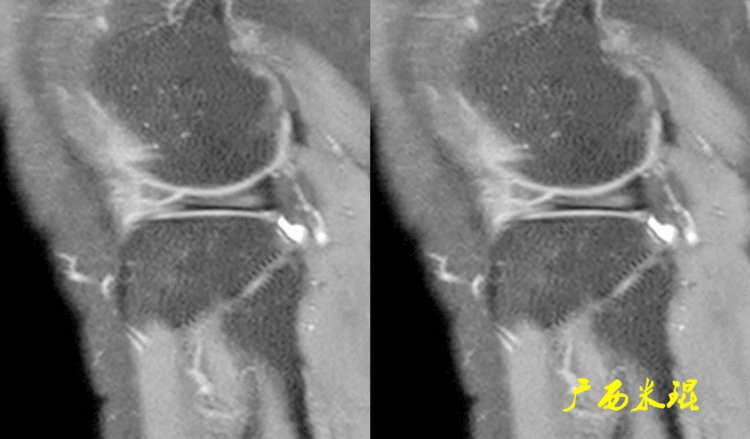

9、半月板股骨韧带外侧半月板后角发出一条纤维带参与后交叉韧带,在接近后交叉韧带时分为两束,分别走形于后交叉韧带的前方和后方,向上伴随后交叉韧带止于股骨内侧髁,前者称为Humphry韧带,后者称为Wrisberg韧带。偶尔也有起自内侧半月板后角的半月板股骨韧带。

半月板股骨韧带起源于外侧半月板后缘中部,起点呈圆索状,在MR上Humphry韧带和Wrisberg韧带并不容易同时见到。

Humphry韧带和Wrisberg韧带起点几乎相同,起点处与外侧半月板后角分隔不明显,但较粗大,也有微小间隙,也常常被误认为是半月板撕裂。

下面这张MR矢状位上也同时见到Humphry韧带和Wrisberg韧带,与外侧半月板后角分隔的高信号影容易误认为是半月板撕裂。

在外侧半月板后根处,半月板股骨韧带由圆索状逐渐转变为扁平状,所以矢状位上半月板上方常常有一菲薄的低信号影,之间为高信号,也容易误认为是半月板撕裂。

下面这张MR冠状位见到的半月板后根与韧带之间为中等信号,也容易误认为是半月板撕裂。